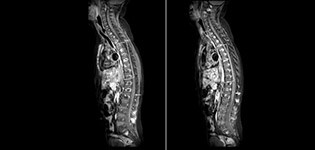

Philips mDIXON TSE is a two-point DIXON technique that separates water and fat signals, for time-efficient fat-free imaging, even in challenging neuro anatomy. “mDIXON TSE has been one of the most significant improvements in imaging sequences that we have utilized to date at PCH,” says Dr. Miller. “Its multi-parametric acquisition allows us to obtain fat suppressed images and equivalent non-fat suppressed T2 images all in the same sequence. In addition, prior methods of fat suppression could be artifactually corrupted by poor patient anatomy or poor operator application, but with mDIXON we now have a robust and reliable method of fat suppression.” Fat saturation is historically challenging at the ends of fields of view, especially in total spine imaging and in difficult patient anatomy such as the lower regions of the neck. “Due to the unique fat suppression capabilities of mDIXON, however, these challenges no long apply,” says Dr. Miller. “We routinely obtain homogeneous fat suppression under virtually all conditions. It has also led to some efficiencies by not having to repeat sequences because of that technical failure.”

“mDIXON TSE has increased our diagnostic confidence in ruling in or ruling out abnormalities in which fat suppression is critical to diagnosis, such as metastatic disease or osseous abnormalities.”

“mDIXON TSE is most useful in patients with lesions or abnormalities in the soft tissues such as the face and neck, and for patients with contrast enhancing abnormalities that are mostly visible with fat suppression,” says Dr. Miller. “All our spine imaging now routinely contains mDIXON water-only T2 images, and this allows us to identify pathology that may be obscured by non-fat suppressed imaging such as injuries of the bone. And it’s not necessary to obtain additional standard TSE T2 images because the in-phase mDIXON images are equivalent to standard TSE T2 images.”